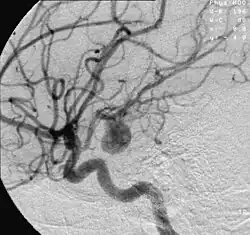

Aneurisma cerebral é a doença na qual um segmento de vaso sanguíneo, quase sempre de uma artéria do Polígono de Willis, encontra-se anormalmente dilatado no encéfalo. A dilatação é causada, em geral, por uma falha muscular da parede de uma artéria, ou muito mais raramente, de uma veia. O tamanho de um aneurisma cerebral é variável. Pode ser pequeno, de poucos milímetros até 1 cm, tamanho médio, até 2 cm e maiores (grandes ou gigantes), atingindo vários centímetros na sua maior extensão. Há diversos formatos, geralmente saculares, mas podem ser também irregulares ou fusiformes.

A caracterização de um aneurisma é realizada por um exame de imagem, tomografia computadorizada, ressonância magnética ou angiografia cerebral, que permitem ao médico identificar a área do cérebro afetada.

O exame padrão ouro para detecção de aneurisma cerebral não é a tomografia ou a ressonância magnética, e sim o cateterismo cerebral de 4 vasos, denominado angiografia cerebral. Entretanto, não costuma ser o primeiro exame realizado.

O tratamento por embolização dos aneurismas cerebrais começa com a inserção de um cateter (pequeno tubo plástico) na raiz da coxa, na artéria femoral na perna do paciente e navegação dele pelos vasos arteriais, passando pela pelva, abdômen, tórax, pescoço e base do crânio até o aneurisma. Através desta viagem pelo corpo, retificadas pelo cateter, pequenas molas ou espirais de platina são inseridas aos poucos dentro do aneurisma. O processo é assistido por meio de imagens radiológicas, visualizadas em um monitor de vídeo. Ao serem destacadas do cateter são desdobradas dentro da luz no aneurisma, ocupando aos poucos o interior, interferindo no fluxo de sangue para o interior do aneurisma, causando coagulação da luz, redução da pressão interna provocada pela pressão sanguínea e prevenindo sua ruptura. As molas são feitas de platina para que eles possam ser visíveis pelo raio x e bastante flexíveis para conformar-se com a forma de aneurisma e tentar evitar que ele se rompa. Um grande número de pacientes no mundo inteiro já foram tratados com molas de platina destacáveis. As micro-molas mais utilizadas para a embolização do aneurisma são as molas destacáveis de Guglielmi.

Os médicos, preferencialmente neurorradiologistas experientes em intervenções por angiografia encefálica, usam a tecnologia de raios-X em tempo real, chamada visualização fluoroscópica (radioscopia), para visualizar o interior dos vasos sanguíneos. As características externas do aneurisma apenas podem ser visibilizadas pela cirurgia aberta.